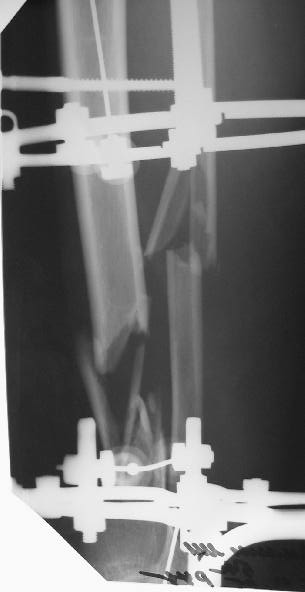

Больному 7 дней назад плита придавила голень стопу. Диагноз Открытый ( 3 б по Каплану) сложный многооскольчатый перелом с выраженным раздроблением н/3 диафиза голени, перелом лодыжек без смещения, перелом основания 5 плюсневой кости с небольшим смещением.

По моему мнению во-первых нужно гешить проблему мягких тканей, для этого провести вторичную и третичную и сколько понадобится обработок при этом удаляя все свободные и инфицированные костные фрагменты - безжалостно и после этого надежное закрытие кожного дефекта с запасом, лучше всего микрохирургический соседистый лоскут . Когда мягкие теани будут готовы в зависимости от размера дефекта можно решить что делать. Лично я предпочитаю замещение дефекта по Илизарову в классическом варианте - остеотомия проксимального отдела тибии и дистальное перемещением с формированием регенерата. Тем более аппарат уже есть. Я бы не стал фиксировать стопу. Судя по снимку дистальный фрагмент достаточно большой, но посмотрим что останется после последней ХО.

А где дефект? Толком не видно.

Согласен с коллегами , что фиксация стопы тут избыточна, и что дефекта не видно.

Учитывая, что травма получена в результате придваливания голени плитой, можно расчитывать на проблемы с заживлением мягких тканей. Поэтому, на мой взгляд, конечно удобнее вести больного в аппарате Илизарова. После полного заживления мягких тканей, при необходимости (дефект, действительно, на данных снимках можно только заподозрить), произвести кортикотомию и постепенно закрыть дефект большеберцовой кости. Можно закрыть дефект путем перемещения фрагмента малоберцовой кости на сосудистой ножке, но технически, для меня это сложнее. По поводу комплектации аппарата - я считаю, что лучше зафиксировать стопу, для того, чтобы исключить микроподвижность в области перелома, поскольку дистальный фрагмент достаточно короткий. Лучше перебдеть, чем недобдеть.

Больного прооперировал, обработку мягких тканей на голени не стал делать, думаю, некроз по краю швов на голени заживет под струпом (рис 3). На стопе удалил некротические ткани, готовлю ее к аутопластике (рис 2).

На дополнительных снимках итраоперационно видна значительная потеря массы (рис 6 рис 1). Хотя на снимках контрольных после операции вроде дефекта значительного нет. Все же придется, как-то замещать дефект костный на голени, думаю подготовить морально больного к повторной операции костной пластике, после заживления ран.